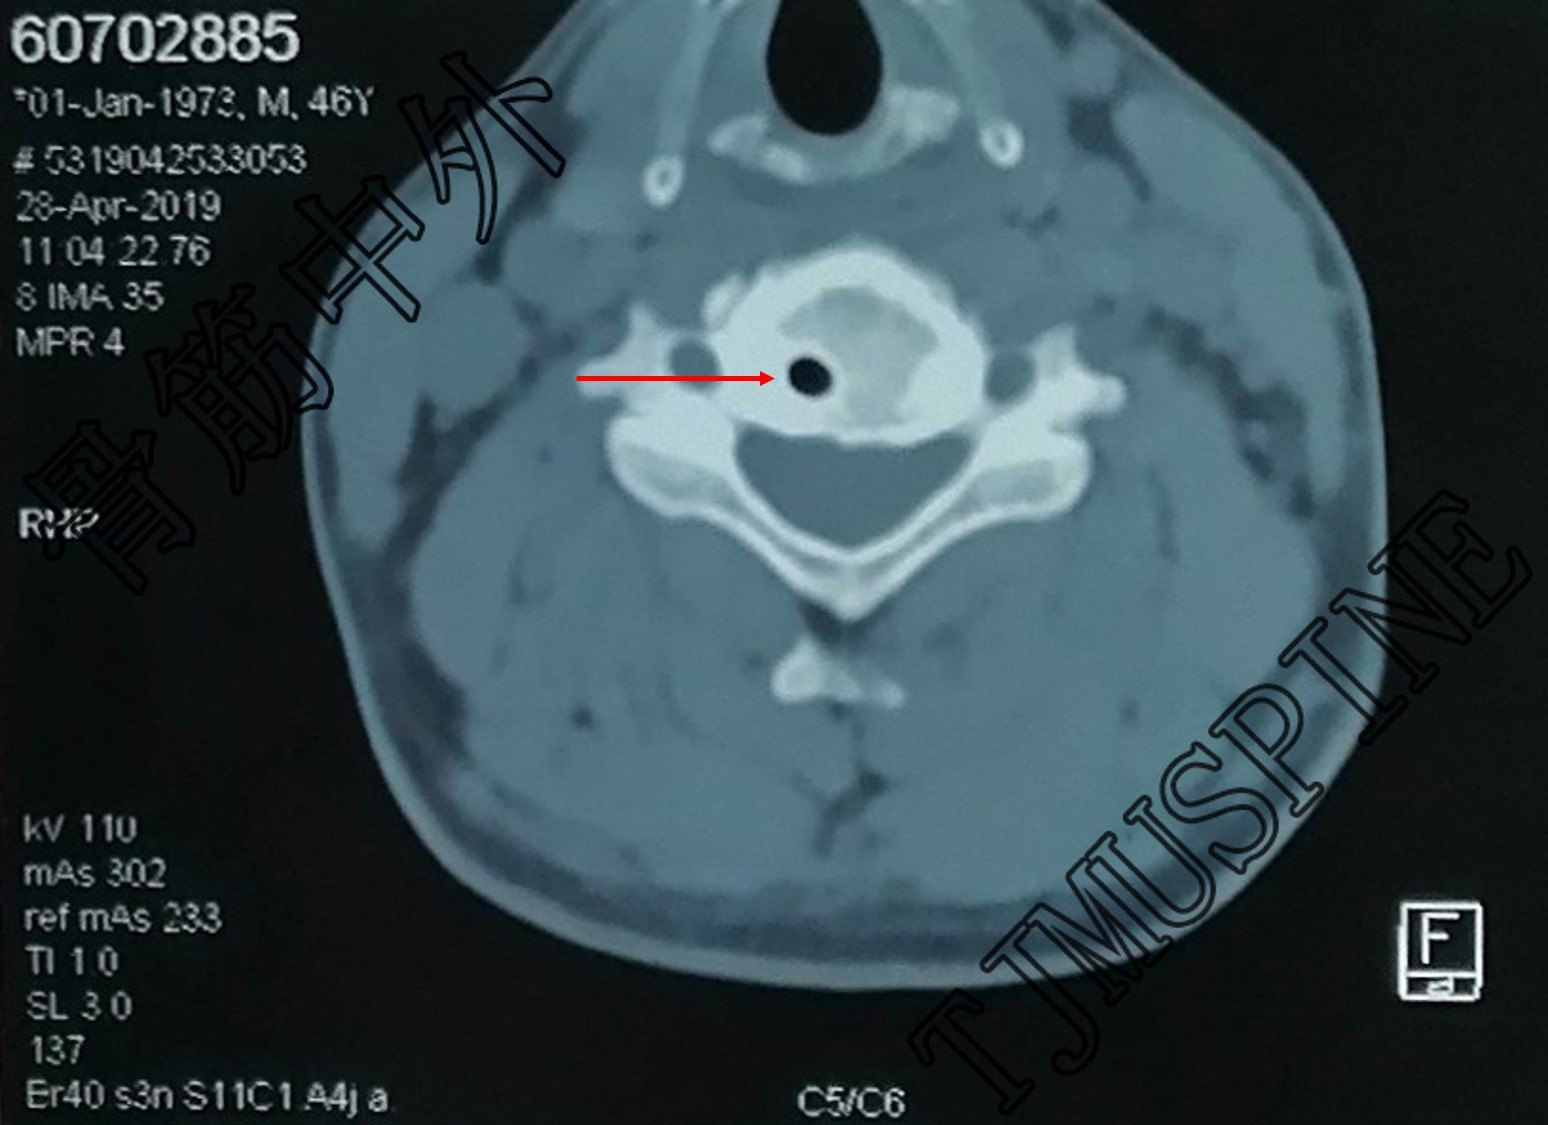

ct颈5 箭头示囊肿.jpg

(颈椎及附件)动脉瘤样骨囊肿 (疑似)

手术方式:显微颈椎4-6髓外硬脊膜囊肿切除,椎板复位重建术.